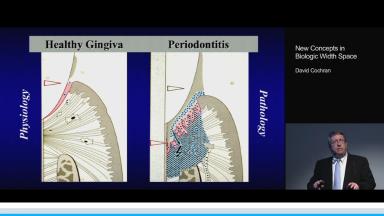

David Cochran discusses the role of biologic width in implant dentistry and its importance for soft and hard tissue stability and health around dental implants as well as for the esthetic outcome of implant-supported reconstructions.

This lecture gives an overview of the relevant comparative anatomy and histology surrounding teeth and implants in healthy or pathologic conditions. Emphasis is placed on creating physiologic relationships and minimizing inflammation. The influence of factors such as the implant-abutment interface, timing of loading, surface characteristics, and the presence of inflammation are discussed based on current evidence.

- describe biologic width around teeth and implants and understand how it differs in healthy and pathologic conditions

- explain the importance of biologic width in preserving peri-implant health and safeguarding an esthetic outcome

- discuss the influence of the implant-abutment interface, loading, and surface characteristics on the dimensions and quality of the supracrestal soft tissue attachment around implants